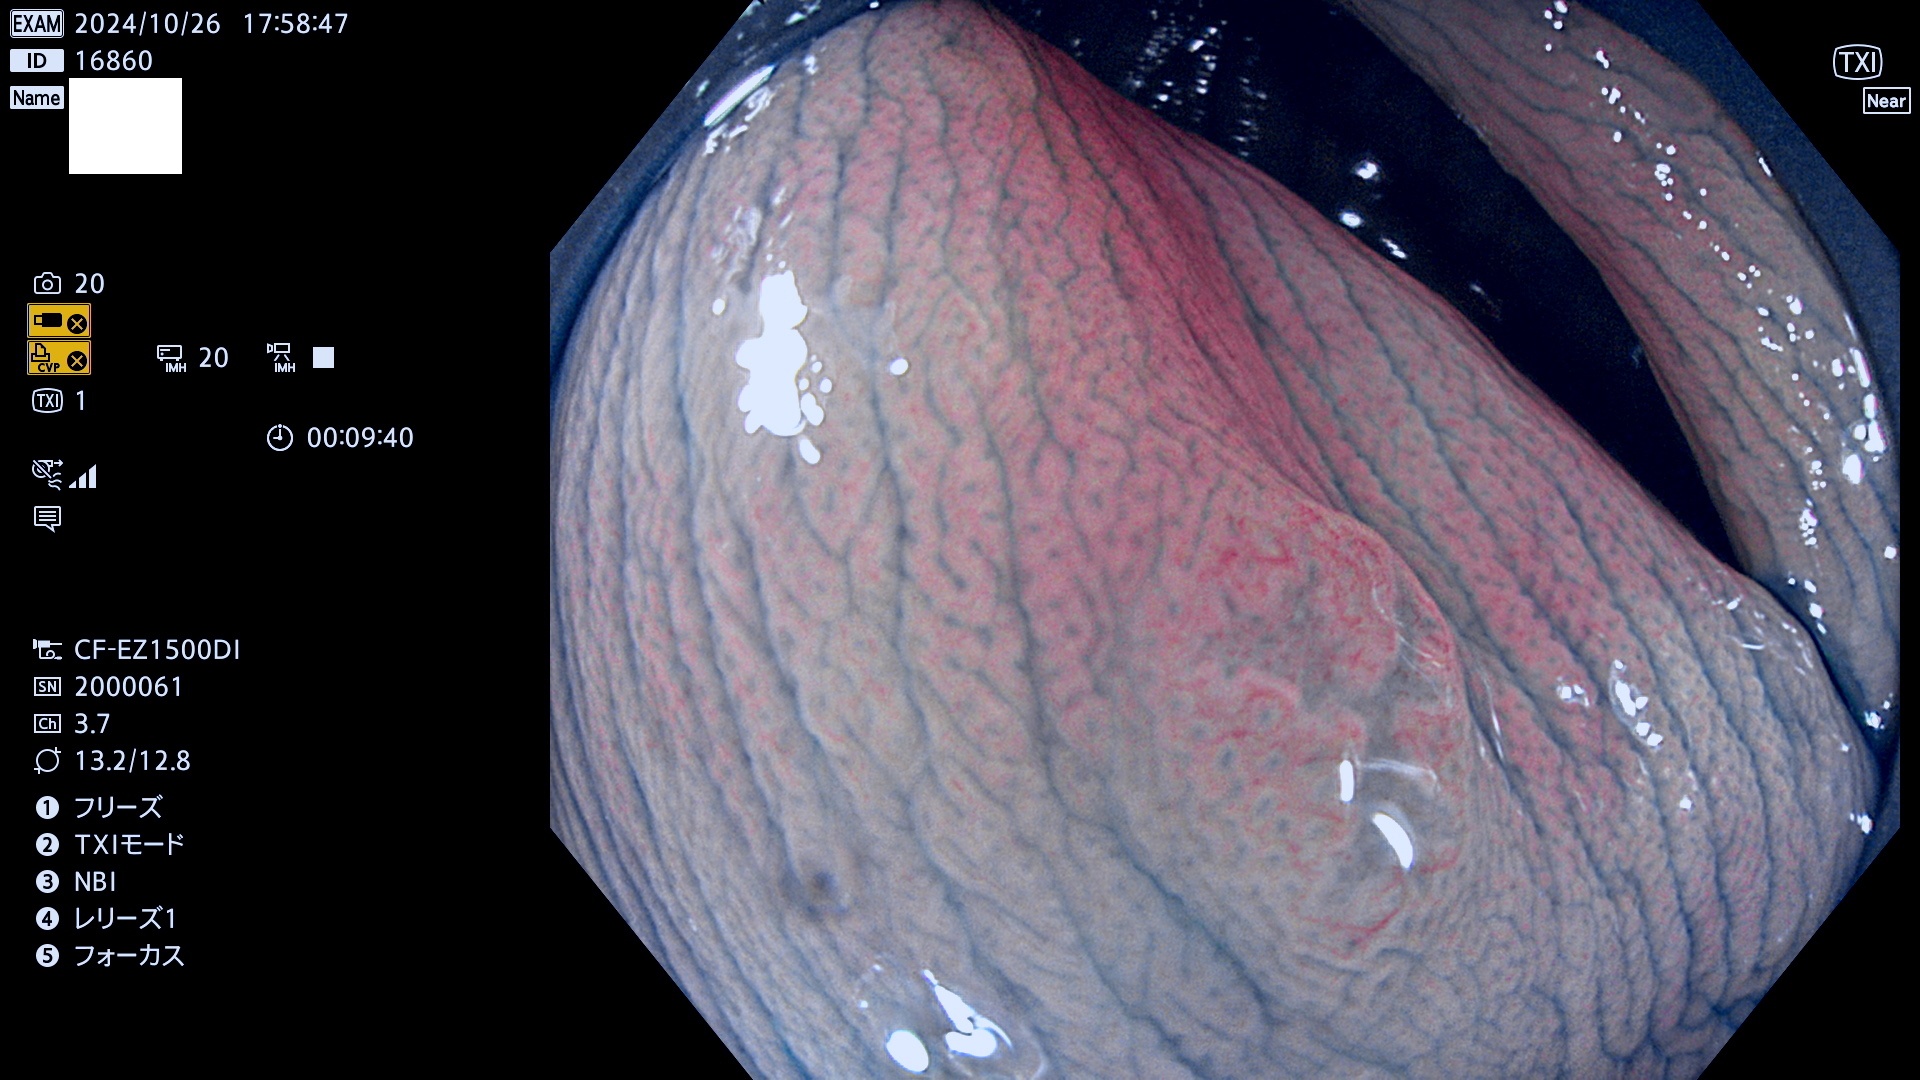

完全に平坦な物をUb、陥凹している物をUcと呼びます。最も発見が難しく危険な病変です。

毎週の検査(木・金・土・日)に発見されたUb、Uc型・腺腫を、その週の日曜の夜にUPし1週間、提示します。

抽出の対象期間 2024年10月24日〜10月27日の4日間(48件の検査)7件 (7/48=15%)